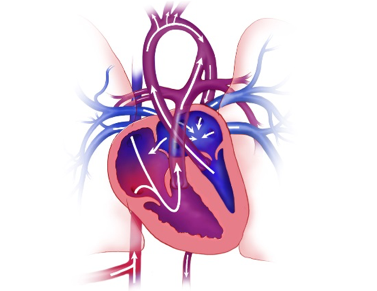

Fetal hypoplastic left heart syndrome (HLHS) and related conditions – We offer three fetal cardiac interventions for babies with small left heart structures, with the type of therapy depending on the fetal heart anatomy.

• For the most severe form of fetal aortic valve stenosis, which may progress to HLHS, we offer a catheter-based intervention called aortic valvuloplasty. Performed by a multidisciplinary team, this procedure consists of placing a small balloon across the fetal aortic valve to enlarge it and to promote blood flow through and growth of the left side of the heart.

• For fetuses with HLHS or mitral valve dysplasia and a restrictive or intact atrial septum, we offer fetal atrial septal intervention. In this catheter-based intervention, either a balloon or a stent is placed across the atrial septum of the heart to decrease the pressure in the left atrium and to help the fetal lungs recover before birth.

• For fetuses with small left-sided structures who may need neonatal heart surgery but do not meet the criteria for the above procedures, we are conducting an experimental study protocol called chronic maternal hyperoxygenation. This treatment involves providing daily home oxygen for expectant mothers to promote fetal left heart growth.